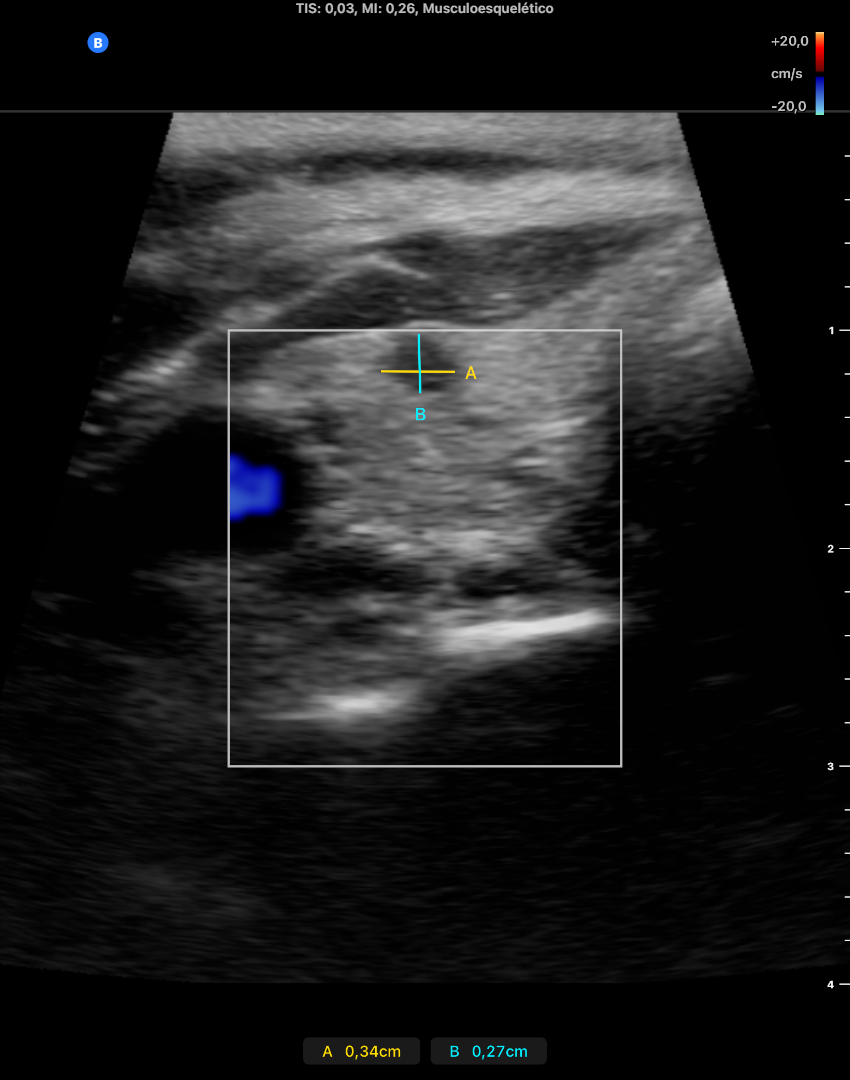

En LTD se objetivan 2 nódulos, uno de ellos quistico y el otro solido bien delimitados, que no captan doppler de 2 x 3 x 2 mm cada uno aproximdamente en diametros APxTxL.